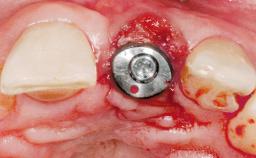

Immediate Placement of an Implant in a Maxillary Left Central Incisor Site

Bone Augmentation Horizontal|Simultaneous

Augmentation Materials Xenogenous|Membrane

Placement Protocol Immediate implant placement

Socket Morphology Single-root socket

Socket Integrity Damage to one or more bone walls

Bone Volume Damage to one or more socket walls